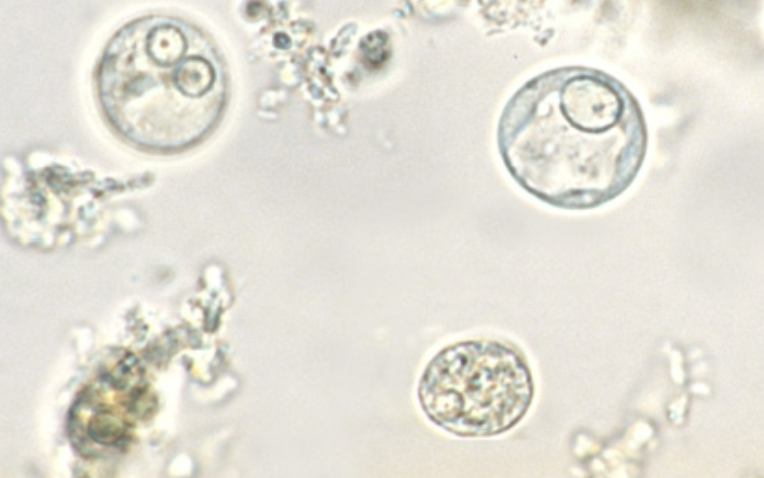

Cyclospora cayetanensis